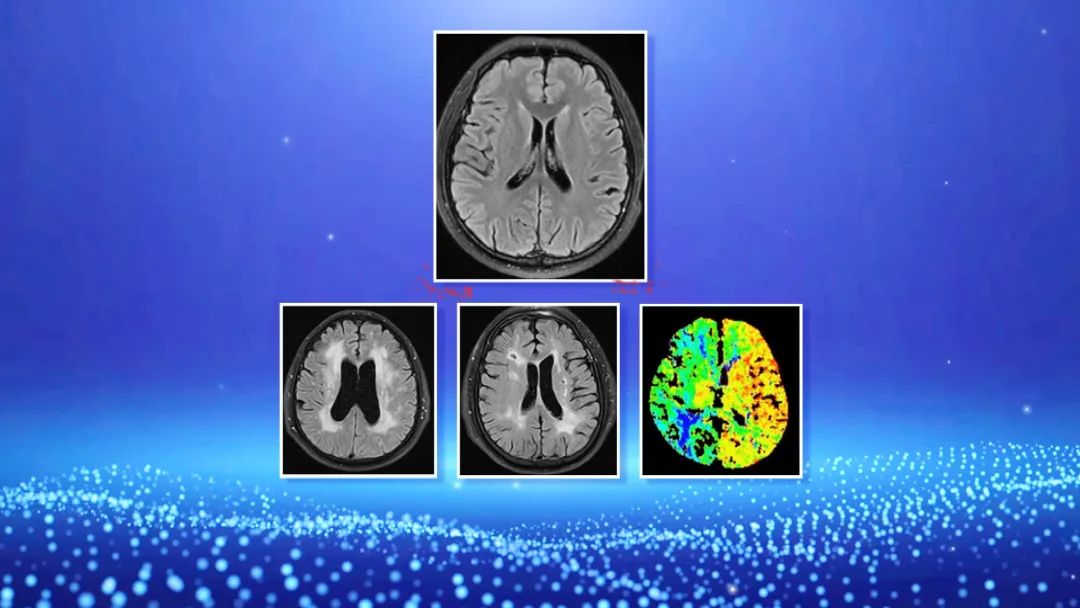

脑部不同的颜色区域分别代表脑血管的供血状态,很多时候这种慢性闭塞引发的缺血我们根本就感觉不到,这种慢性缺血的出现不会直接发生紧急状态,甚至缓慢的缺血还会促使侧支循环建立,进一步出现代偿去补救脑部的缺血,但是“慢刀子”更伤人,这种自救的同时也会掩盖脑血管闭塞的问题,让疾病一步步走到严重阶段,所以这种慢脑梗比急性脑梗更危险!